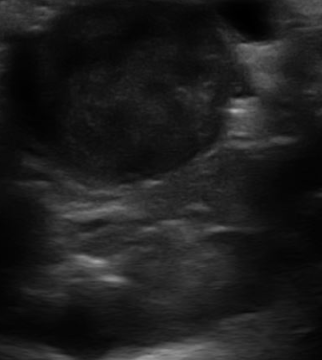

10세 미니어처 푸들 김장군이가 최근 다뇨, 다음, 복부 팽만, 무기력, 반복적인 요로감염 등 쿠싱증후군(Cushing’s disease)이 의심되는 증상을 보이고 있습니다. 현재 복용 약물은 관절염 치료를 위한 리마딜, 종합 비타민, 요실금 치료를 위한 diethylstilbestrol입니다. 원내 혈액검사에서 ALP가 1,200으로 상승되어 있었습니다. ACTH 자극 검사는 다음과 같은 결과를 보였습니다. • 투여 전: 12 (0–6) mcg/dL • 투여 후: 37 (6–15) mcg/dL 복부 초음파에서 양측 부신의 대칭적 비대가 관찰되었습니다. 보호자가 질병의 원인에 대해 질문했을 때, 가장 가능성 높은 설명은 무엇입니까?